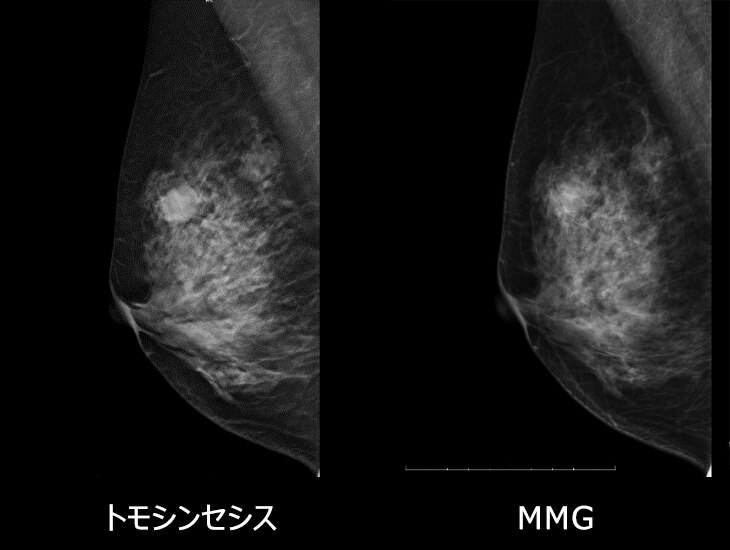

• MMG所見:左乳房M/L,I域 41㎜楕円形等濃度腫瘤あり、スピキュラ+

• トモシンセシス:M領域 構築の乱れが顕著化

• 病理組織:Invasive ductal carcinoma scirrhous type